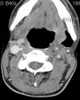

Neck infection